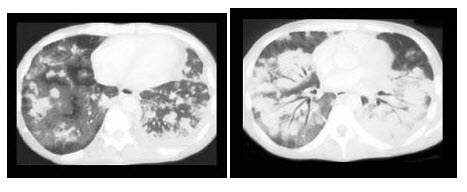

30、单项选择题 关于透光率(T)的叙述,错误的是()

患者26岁,男性,有慢性肺病,剧烈腹痛,汗液正常,最可能的诊断是()

A.过敏性支气管肺曲霉菌病